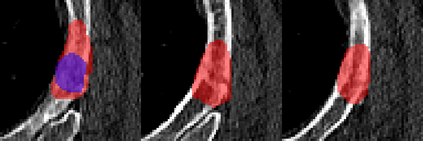

Rib fractures are a common and potentially severe injury that can be challenging and labor-intensive to detect in CT scans. While there have been efforts to address this field, the lack of large-scale annotated datasets and evaluation benchmarks has hindered the development and validation of deep learning algorithms. To address this issue, the RibFrac Challenge was introduced, providing a benchmark dataset of over 5,000 rib fractures from 660 CT scans, with voxel-level instance mask annotations and diagnosis labels for four clinical categories (buckle, nondisplaced, displaced, or segmental). The challenge includes two tracks: a detection (instance segmentation) track evaluated by an FROC-style metric and a classification track evaluated by an F1-style metric. During the MICCAI 2020 challenge period, 243 results were evaluated, and seven teams were invited to participate in the challenge summary. The analysis revealed that several top rib fracture detection solutions achieved performance comparable or even better than human experts. Nevertheless, the current rib fracture classification solutions are hardly clinically applicable, which can be an interesting area in the future. As an active benchmark and research resource, the data and online evaluation of the RibFrac Challenge are available at the challenge website. As an independent contribution, we have also extended our previous internal baseline by incorporating recent advancements in large-scale pretrained networks and point-based rib segmentation techniques. The resulting FracNet+ demonstrates competitive performance in rib fracture detection, which lays a foundation for further research and development in AI-assisted rib fracture detection and diagnosis.